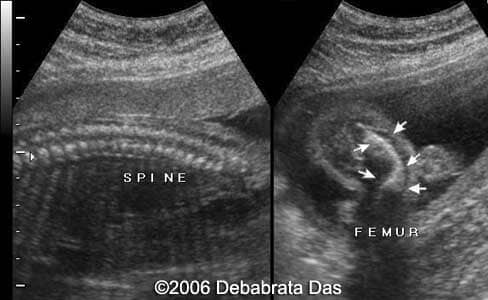

Case report: This is a 22-year-old primigravida referred for a routine anomaly scan at 22 weeks. She has a family history of consanguinity. Our scan revealed significant lower limb shortening. The femur and tibia showed bilateral bowing. Fibulae appeared normal. The mineralization of the bones was adequate. The upper limbs seemed normal. The axial skeleton showed 11 pair of ribs. No abnormal fetal chest narrowing. Fetal facial features were unremarkable. A camptomelic dysplasia was suspected. The pregnancy was interrupted. The radiograms showed bilateral bowing and shortening of tibia and femur.

The characteristic skeletal features are short and ventrally bowed tibia and femurs, hypoplastic or absent fibulas and hypoplastic scapulae. The gene responsible for camptomelic dysplasia is sex determining protein homeobox 9 or SOX9 which is expressed in the fetal brain, testis and perichondrium and chondrocytes of long bones / ribs.